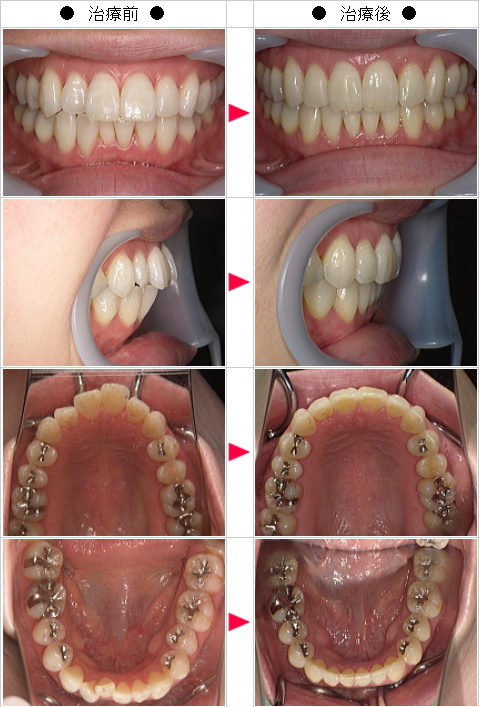

☆出っ歯矯正の治療症例[R.M様 37歳 女性]